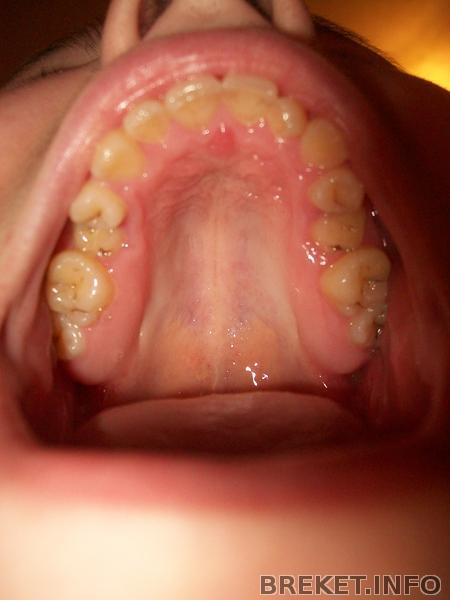

ВЧ - 3 мес.НЧ - 2 мес. все не так уж плохо)

Снова была на приеме у своей ортофеи ) Сменили дуги и она сказал,что все идет нормально..даже хорошо

ВЧ хорошо подравнялась,клык двигается в верном направлении.

Воооообщем, вот фотки.

vch-_1_mesyac.jpg

vch-3_mesyaca._nch-_2.jpg

Но все равно ещё симметрия нарушена и НЧ кривая.

А как вы считаете,есть продвижения какие-нибудь??